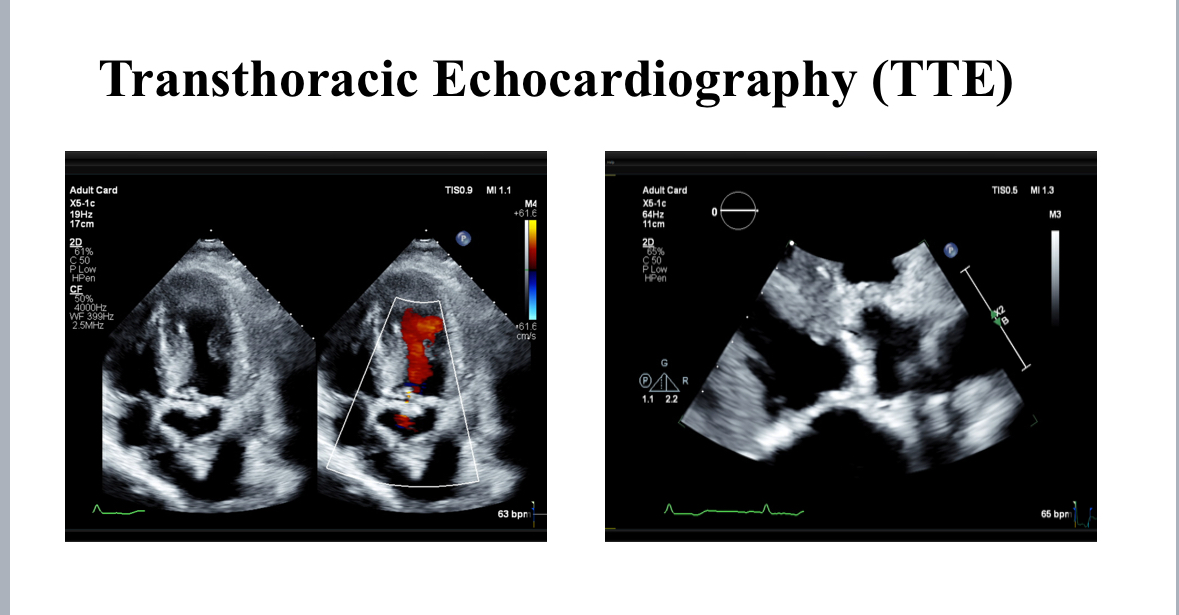

creatinine 150 mcmol/L, estimated glomerular filtration rate: 38 mL/min/1.73m2, creatinine clearance: 28 mL/ min). In 1998, he underwent CABG with LIMA to LAD, and SVG to D1and OM1. In 2020, he underwent PCI and stent to LIMA-LAD, RCA and SVG to OM1.Transthoracic echocardiography showed an ejection fraction of 55%, severely calcified tricuspid aortic valve, aortic valve area of 0.9 cm2, peak gradient of -- mmHg, mean gradient of – mmHg, Vmax – and dimensionless index of 0.22. ECG showed normal sinus rhythm and a heart rate of 55 beat per minute.

Post-TAVI aortography confirmed proper valve positioning with only a trivial paravalvular leak (PVL). The access sites were successfully closed using ProGlide and Angio-Seal devices. A total of 50 cc of Gadobutrol was used. Pre-discharge transthoracic echocardiography (TTE) confirmed good transcatheter heart valve (THV) positioning, no PVL, and a peak gradient of 6 mmHg. Renal function tests performed one week post-procedure showed no deterioration, with a creatinine level of 156 µmol/L.

Post-TAVI aortography confirmed proper valve positioning with only a trivial paravalvular leak (PVL). The access sites were successfully closed using ProGlide and Angio-Seal devices. A total of 50 cc of Gadobutrol was used. Pre-discharge transthoracic echocardiography (TTE) confirmed good transcatheter heart valve (THV) positioning, no PVL, and a peak gradient of 6 mmHg. Renal function tests performed one week post-procedure showed no deterioration, with a creatinine level of 156 µmol/L.